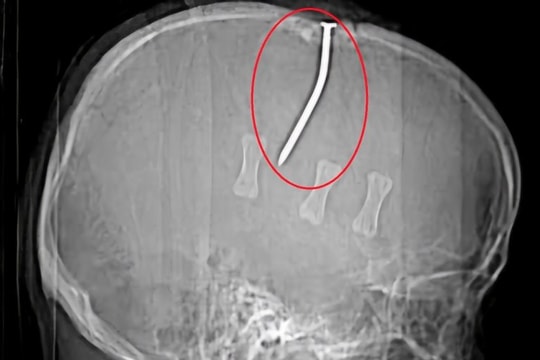

Người đàn ông bị đinh sắt 10cm đóng vào đỉnh đầu

Ngày 22/4, theo thông tin từ Bệnh viện Hữu nghị Việt Tiệp (TP. Hải Phòng), bệnh viện vừa cấp cứu thành công một bệnh nhân bị đinh sắt dài 10cm đâm xuyên đỉnh đầu.